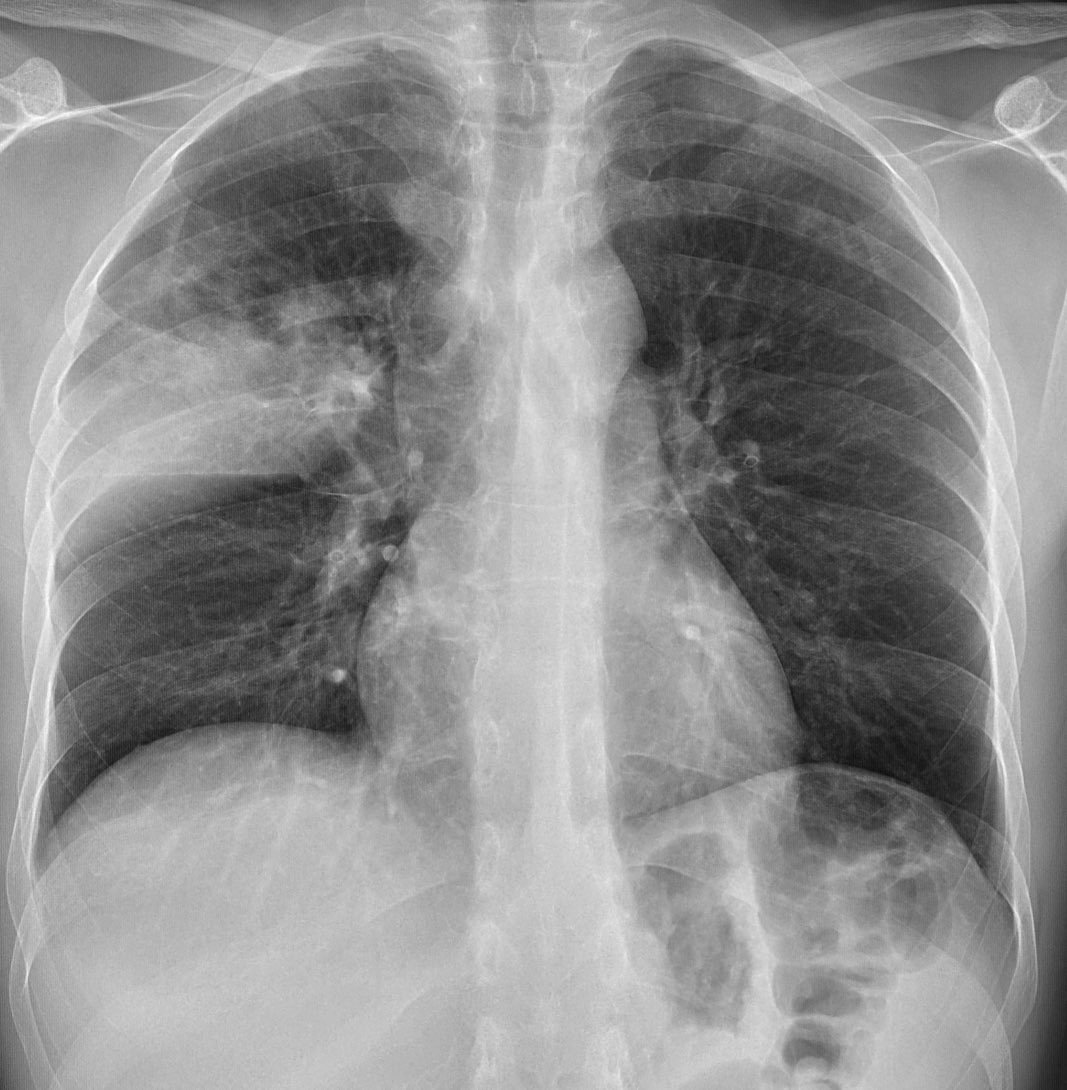

This is classic lobar pneumonia, involving the right upper lobe. Sometimes pna can look mass like on one of the views, but often the other view shows it spreading out along a fissure or other pleural boundary, fading along the non pleural margin, more typical of pna than cancer.

The patient is a 45 yo male. Acute kidney injury and ? Pneumonia. The first image was at presentation. There is peribronchial consolidation with a nice perilobular appearance peripherally. Looks like organising pna. Cause could be infection, vaping, drug reaction, CTD...